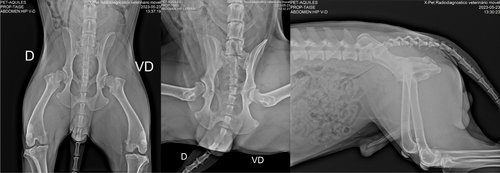

Com o passar do tempo percebemos que ele mancava de uma patinha, mas logo depois voltava ao normal. Certo dia ele comecou a mancar muito e levamos ao veterinário onde foi avaliado e medicado. Dias se passaram e nada de resultado. Fizemos o raio-x onde foi constatado que Aquiles tinha displasia bilateral nos dois quadris.

Imagens e diagnóstico do raio-x: